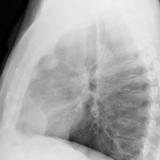

Case 8b Thymoma Lat

Date: 03/27/2009

Views: 14092